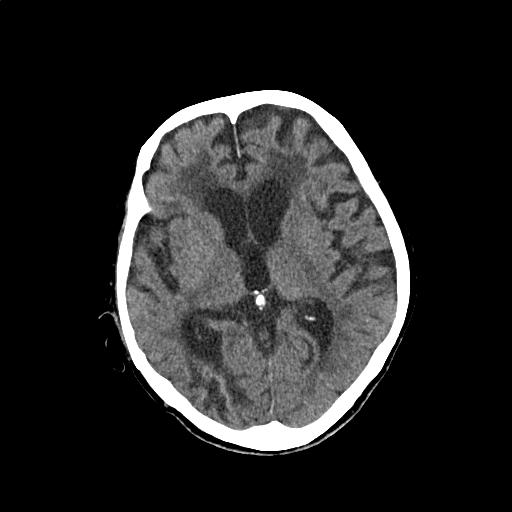

症例画像9

画像診断検査結果9

【画像診断検査結果】

CTスライス画像

(Findings)

頭蓋内に明らかな出血や急性期脳梗塞を疑う所見は認めない。

右後頭葉に陳旧性脳梗塞を疑う低吸収域を認めるが、前回と比較して著変はない。

大脳白質の慢性虚血性変化および脳萎縮は年齢相応と考える。

(Impression)

明らかな急性期病変を疑う所見は認めない。